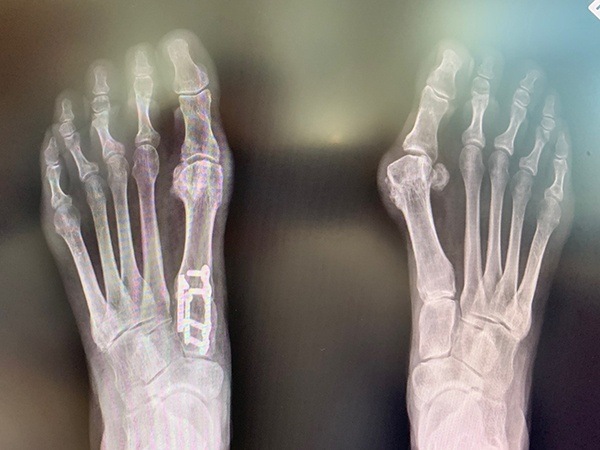

Photo Gallery

Click on the below thumbnails for enlarged view.